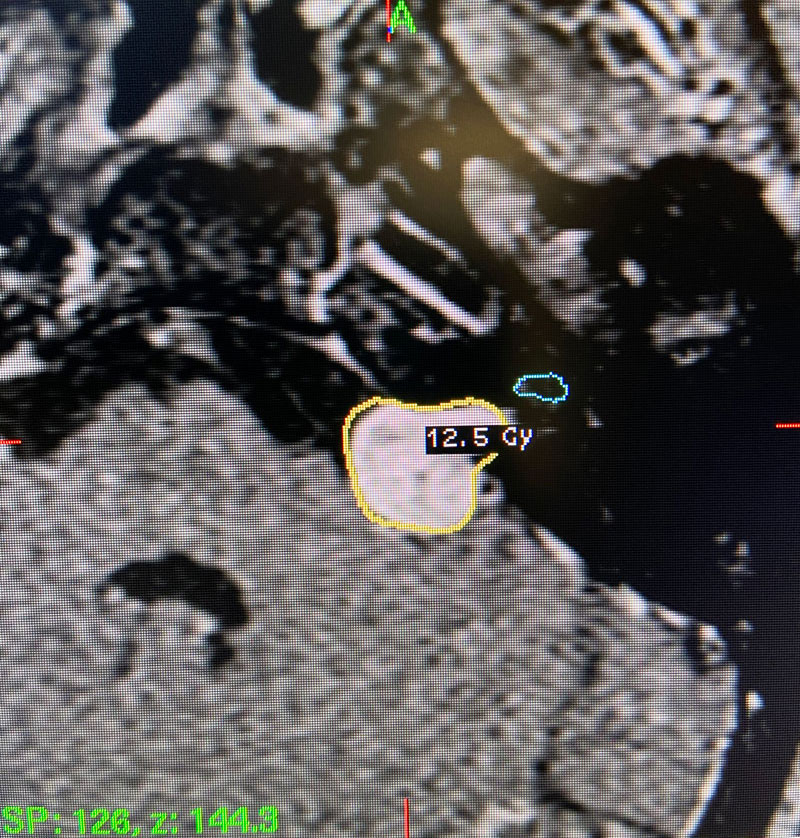

Technical Aspects of Gamma Knife Treatment: Dose to the tumor is set to 12-13 Gy to the edge of the tumor. The 50% isodose line is set to the edge of the tumor. Dosing under 12Gy is less effective at tumor control, and dosing over 13Gy puts the facial nerve at risk. There is evidence that the radiation dose to the cochlea affects whether hearing will ultimately be preserved. As such, if there is meaningful hearing at the time of treatment, the mean cochlear dose should be set to 4.2Gy or less. The cochlea is separately contoured at the time of treatment off fine cut T2 sequences which are then fused to the post contrast T1 images.

This patient: This patient had a moderate sized , symptomatic acoustic neuroma with serviceable hearing. Gamma Knife was recommended. A Gamma Knife treatment was performed by Dr. Michael Brisman. The radiation oncologist was Dr. Leester Wu. A treatment plan was made that was very conformal to the tumor. A prescription of 12.5Gy to the 50% isodose line was delivered. This plan involved a mean cochlear dose of 3.5Gy.

Image 2: Intra-operative Gamma Knife treatment planning for the left acoustic neuroma. A tightly conformal treatment is set for 12.5Gy to the 50% isodose line. The cochlea has also been contoured, based off a fused image from a fine cut T2 sequence.